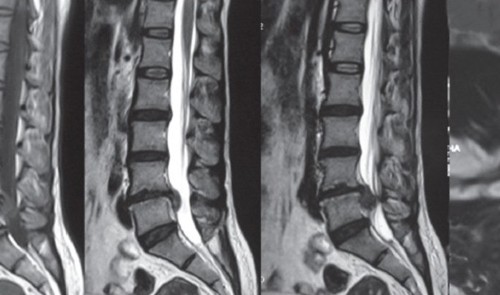

Hryggsúlan er sett saman úr 26 smábeinum sem kallast hryggjarliðir og brjóskþófum sem tengja beinin saman. Þessir þættir raðast upp í súlu sem umlykur mænuna og styður við... Lesa meira